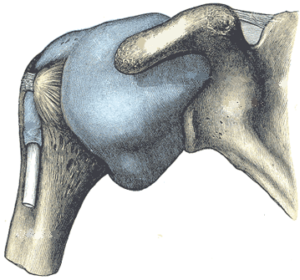

In questi casi, è possibile che ci sia di mezzo la borsa sottoacromiondeltoidea (SAD). Quando questa borsa è infiammata (borsite) e/o imbibita, congestionata, con versamento insomma … ebbene, risolvere i disturbi in modo tradizionale diventa inefficace.

L’allineamento frizionato riesce a ristabilire l’equilibrio termico-idrico di questa borsa, gli effetti sono una risoluzione del dolore nella maggior parte dei casi e il ripristino della mobilità.